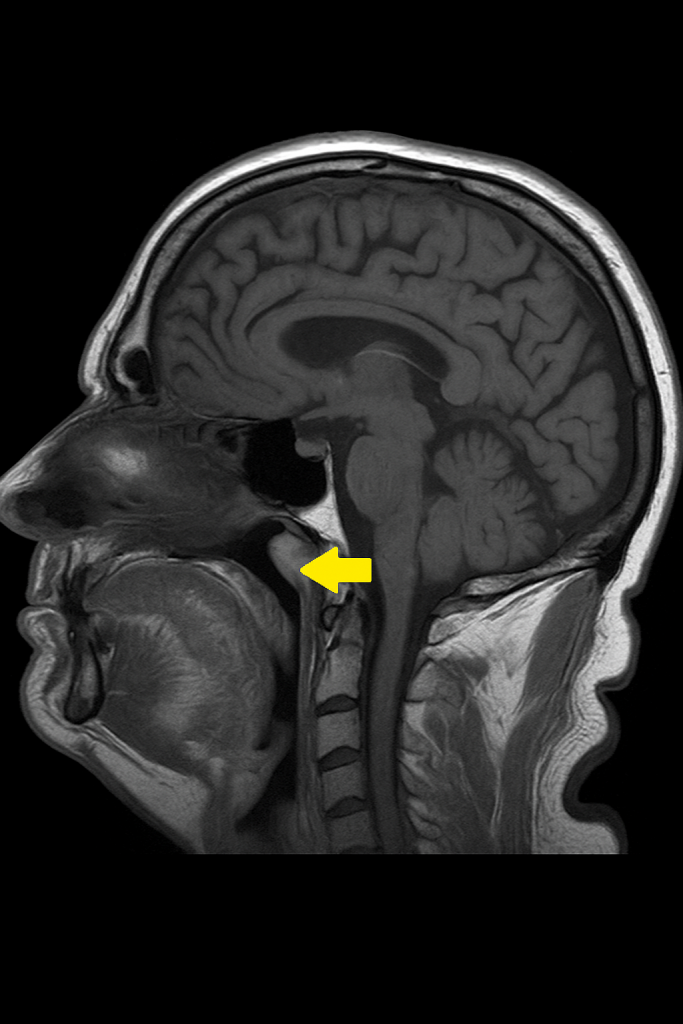

Tornwaldt kistleri genellikle nazofarenksin dorsal orta hattında, üst servikal omurga düzeyine yakın yerleşim gösterir. Kistin duvarı genellikle kalınlaşmıştır ve içi mukoid materyal ile doludur. Enfekte formlarında içerik pürülan hale gelir. Histolojik olarak kist duvarı respiratuar tipte silyalı psödostratifiye epitel ile döşelidir ve çoğu zaman kronik inflamatuar hücre infiltrasyonları gözlenebilir.

- Manyetik Rezonans Görüntüleme (MRG): Yumuşak doku çözünürlüğü yüksek olduğu için tercih edilir. T2-ağırlıklı sekanslarda hiperintens kistik lezyon izlenir.